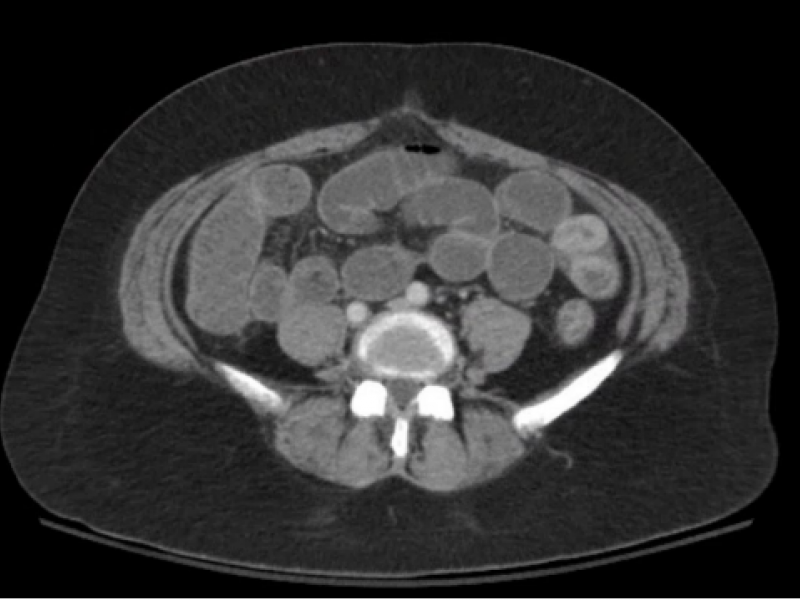

A 45 yo female with a hx of Crohn's disease and multiple